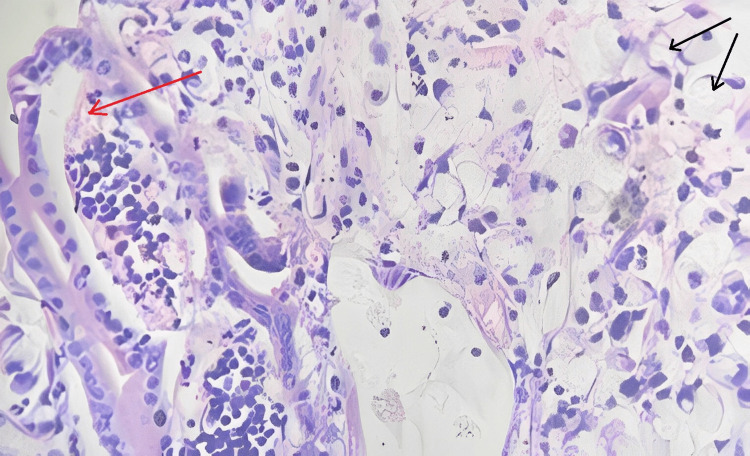

Microscopic findings

Sections studied from the ampullary growth revealed mucosa lined by columnar epithelium infiltrated by diffuse sheets of signet ring cells. These cells had vacuolated cytoplasm and hyperchromatic pleomorphic eccentric nuclei. Areas of mucin pools were seen. A dense inflammatory infiltrate was seen in lamina propria, submucosa, and muscularis propria. The serosa showed inflammatory cells and congested blood vessels. Sections studied from both proximal and distal margins were free from tumor invasion. Sections studied from the duodenum, gall bladder, pancreas, mesentery, and CBD were free from tumor invasion.

Signet ring cell adenocarcinoma of the ampulla of Vater (TisN0M0) Stage 0 (Figures 2–4).